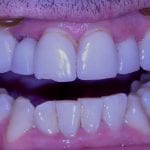

Immediate Post Op